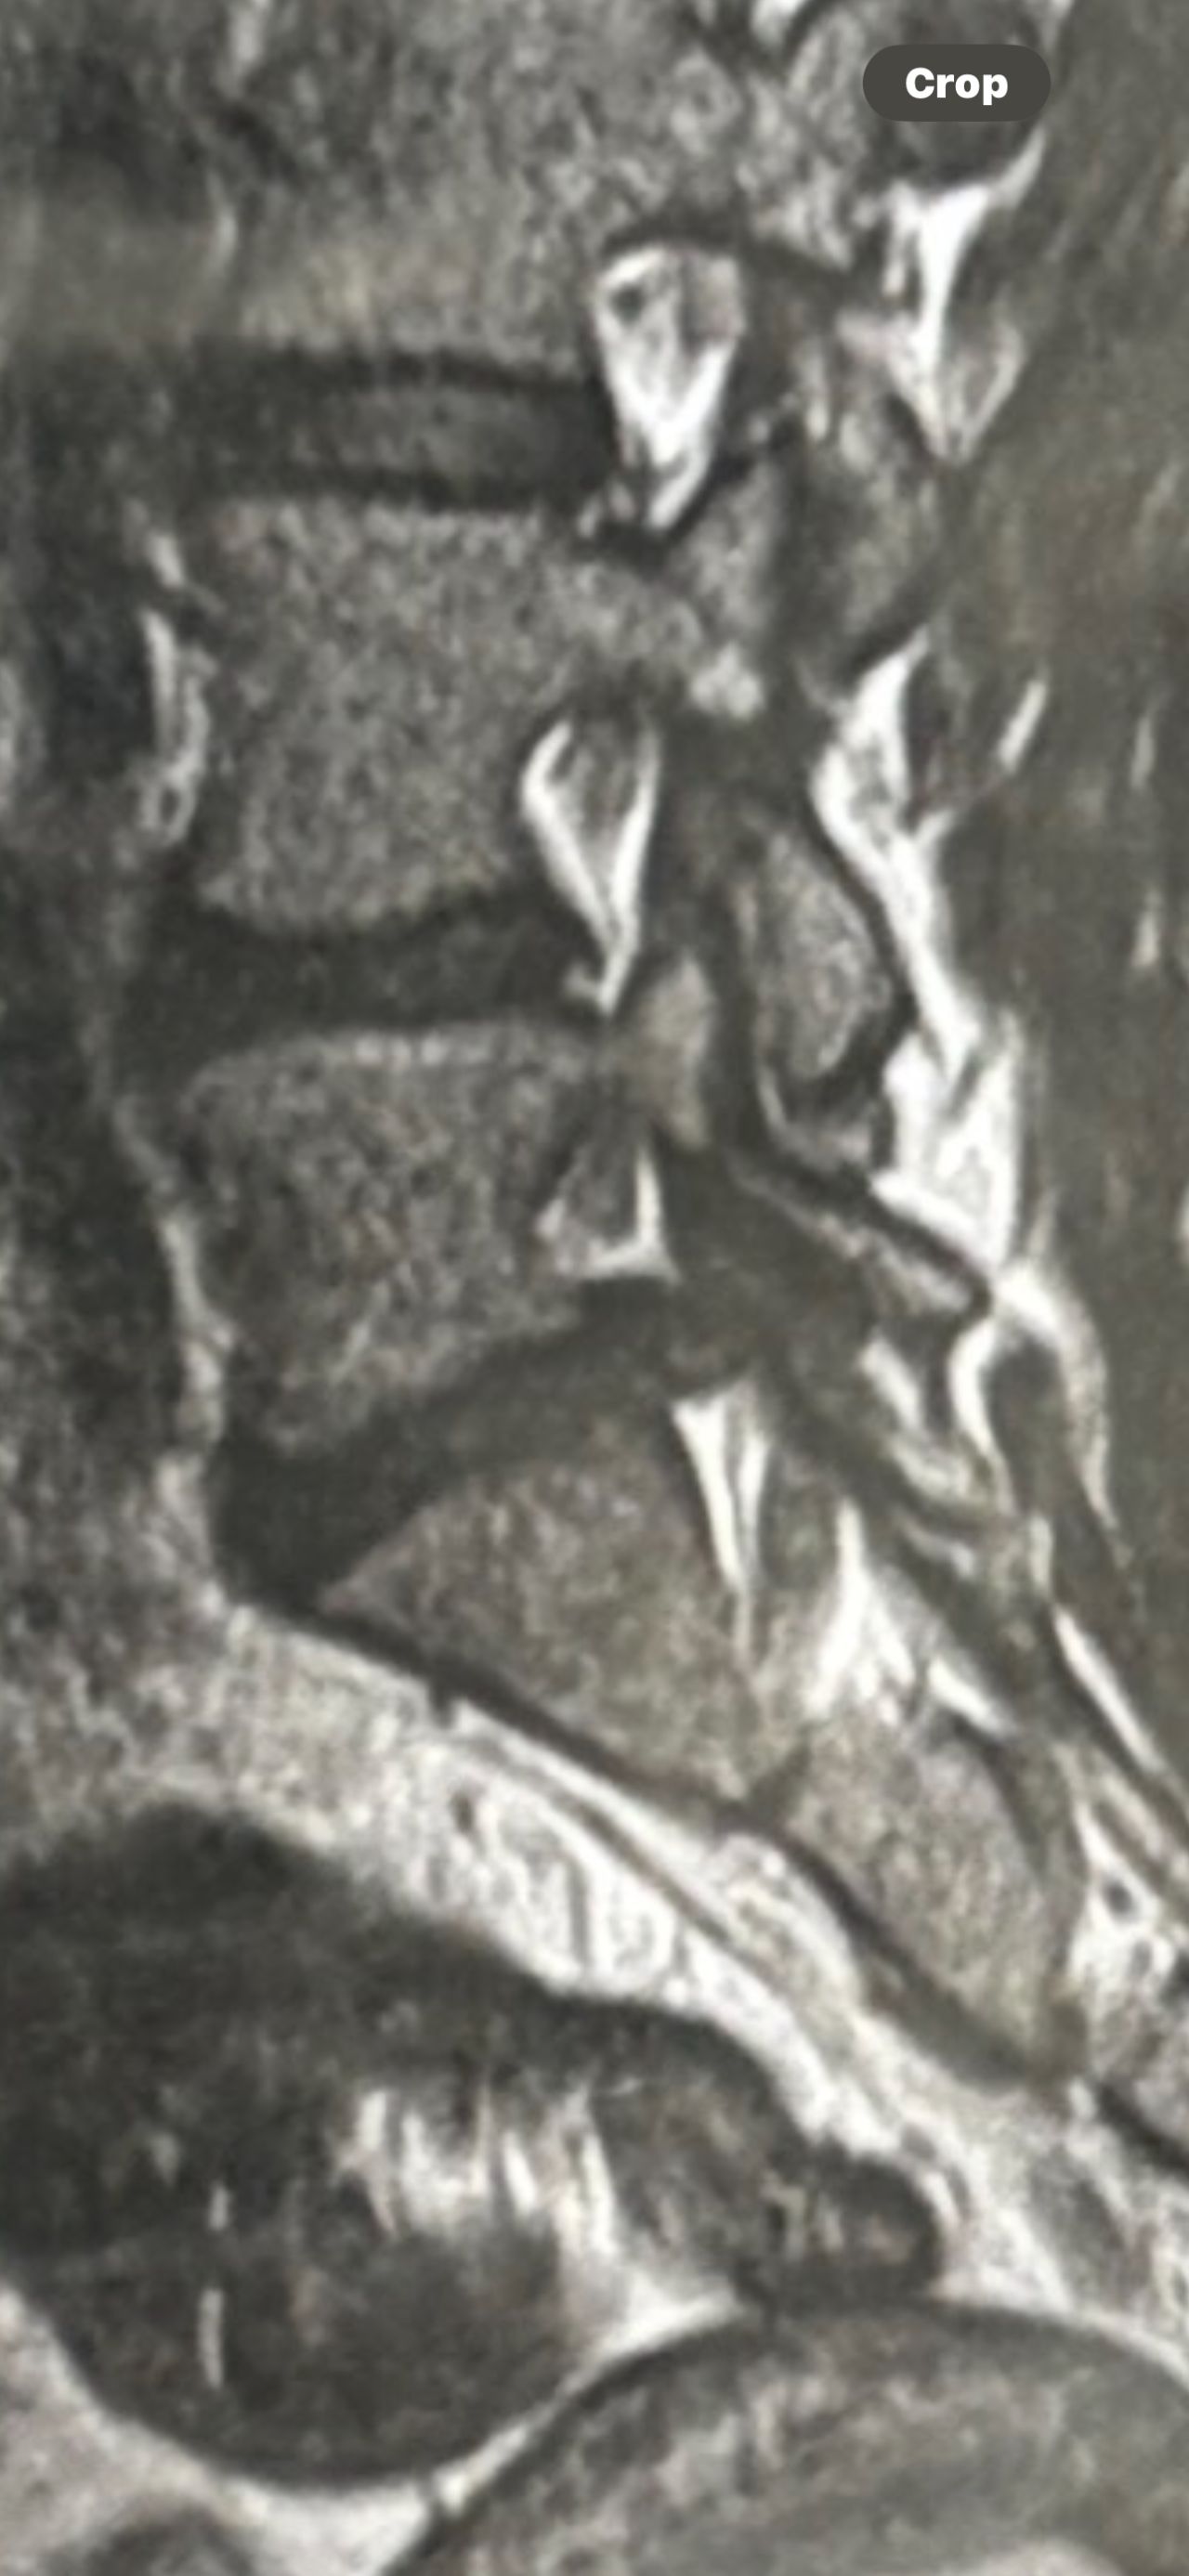

41 years old man presented to my clinic in October 2023 with acute and sever R neck pain with radicular pain to his R upper extremity along C6 dematom since 2 weeks ago. Examination didn’t show any upper motor signs. Was suggested urgent surgery

I ordered EMG/ NCV : showed mild R C6, C7 irritation without any active axonal loss

In his MRI was reported R. para R. IVF Massive extrusion. I decided to control his pain and manage this patient with reevaluation of patient every other session. For 5 sessions i just used acupuncture and laser and IFC and mild adjustments to his R. T3-T7 and mild arthosteem to above and below involved segment. Cervical adjustment considered contraindicated for this patient. From session 6th- 8th i started to use mild/gentle cervical decompression. He used soft cervical collar all the time. His pain decreased by 80 percent

I gave him cervical traction pump to be used 3-5 times per day at home for the next 3 months and i released the patient. He was evaluated every week once for one month and after that every 2 weeks. After 3 month I repeated MRI. Size of the herniated disc was reduced greater than 50 percent. Asked him to do another mri in 6 months

In general: Precise selection of the patients, examination,diagnosis, plan of management, reevaluation and treatment can be done by doctors of chiropractic for the patients with spinal disc herniation and stenosis Moreover giving reasonable time to these kind of patients under direct supervision by their chiropractic doctors can prevent unnecessary surgery. Proper selection of these kind of patients is another important fact that can be done precisely by chiropractors.

MRIs before and after proper management of this patient: